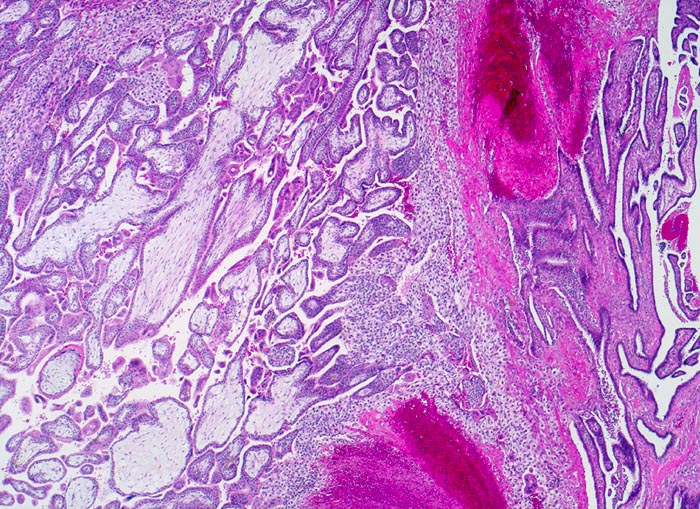

AP/ Tubargravidität

Tubargravidität

Tuba uterina